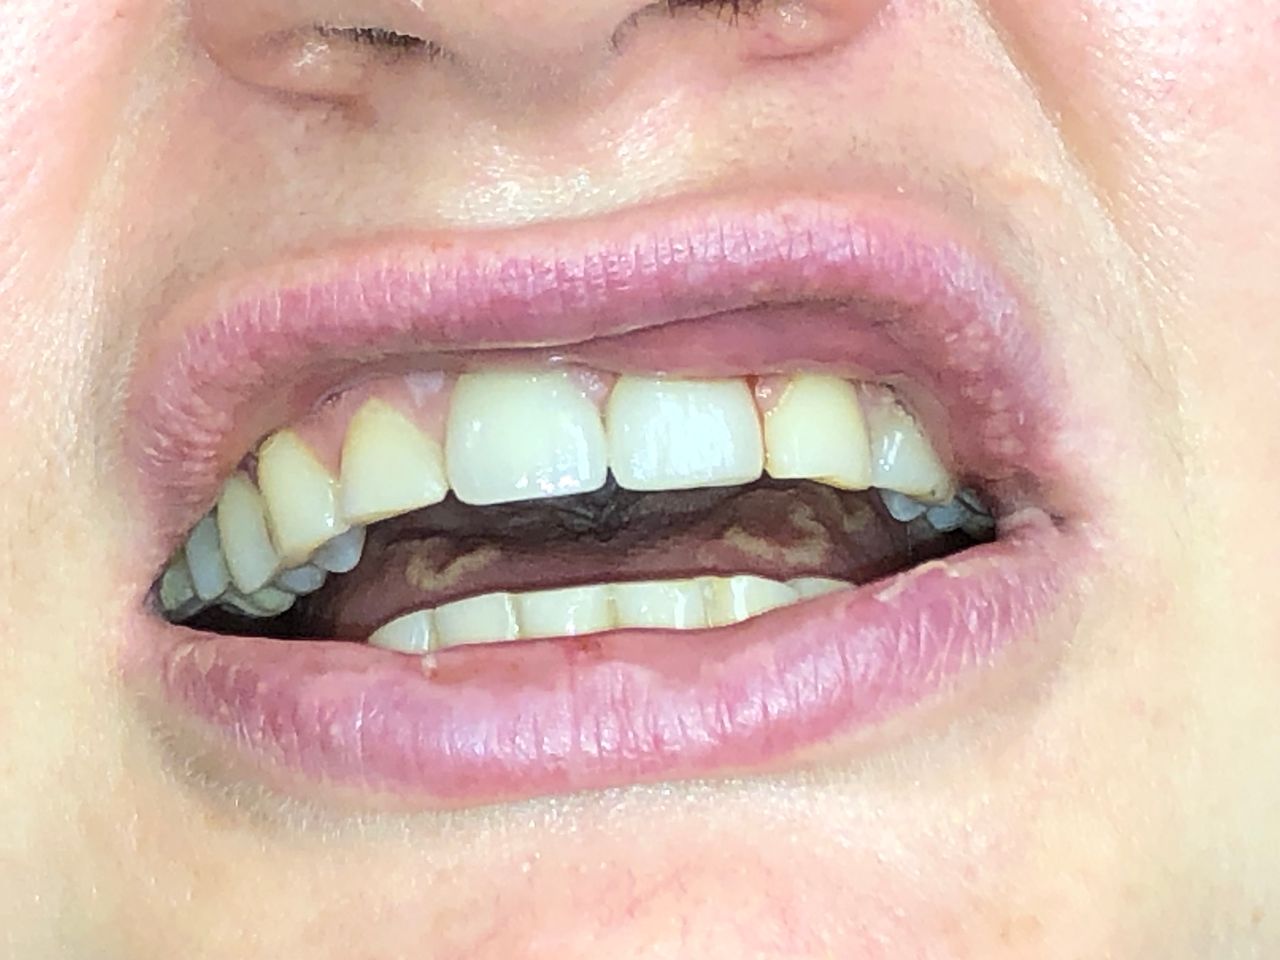

Foto e video